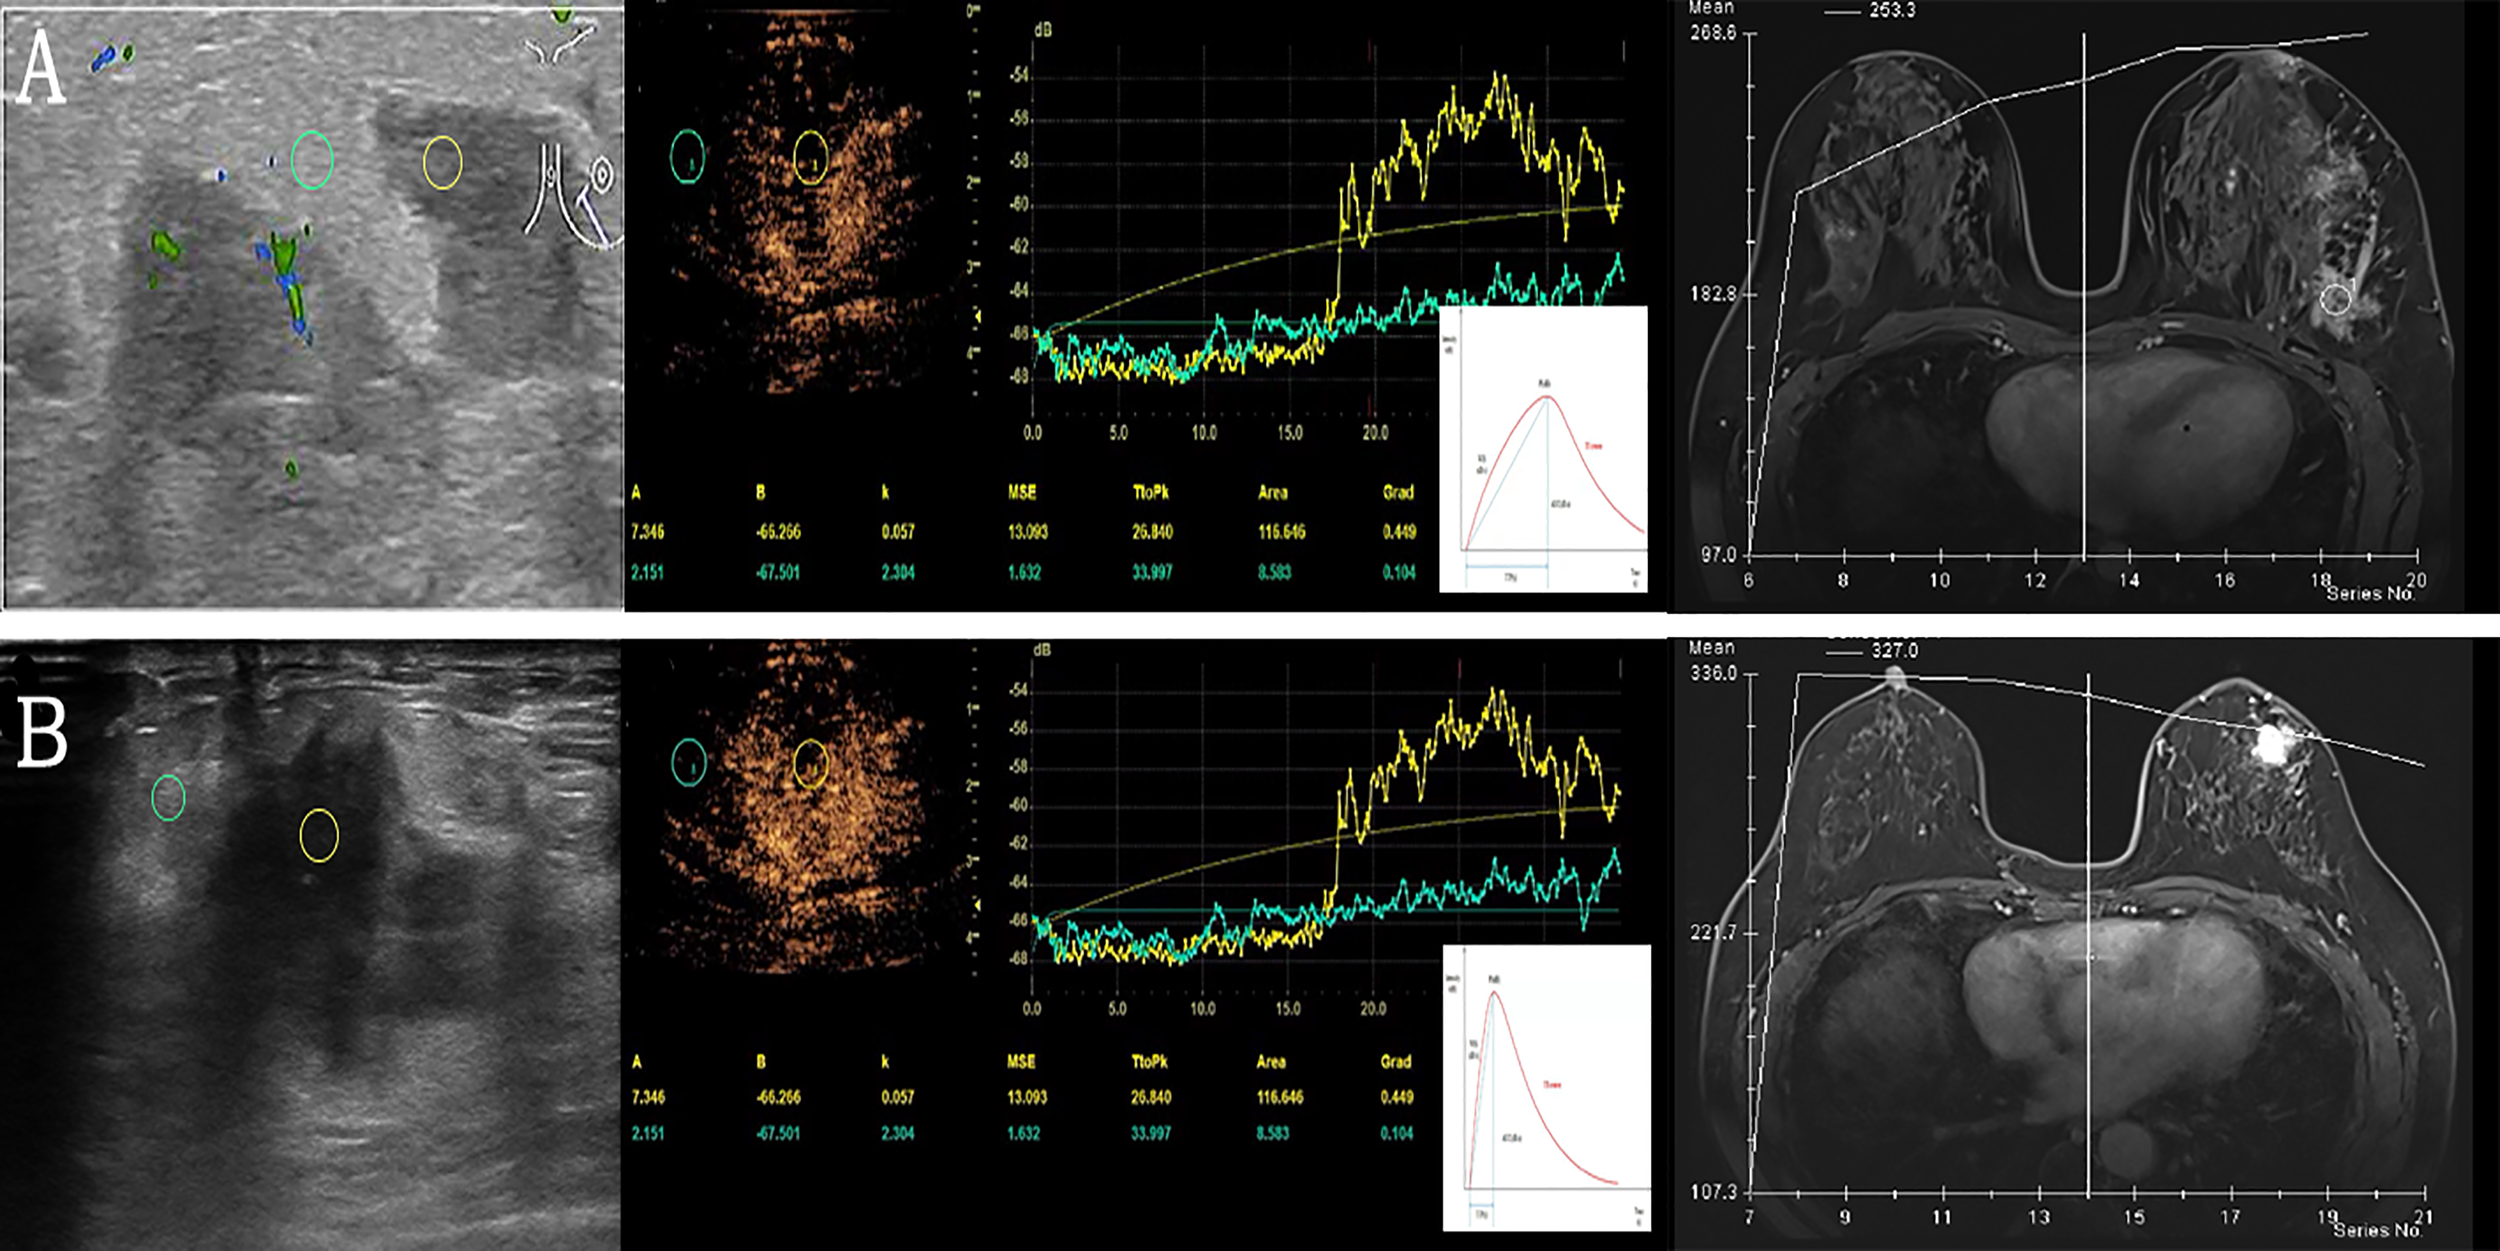

Figure 3

Examples of quantitative data acquisition using ROI. (A) Granulomatous lobular mastitis in a 28-year-old female. Moderate enhancement of the lesion (yellow ROI) compared to minimal enhancement in surrounding breast tissue (green ROI). Gradual enhancement and a gradual wash out of contrast agent (corresponding TIC below) versus TIC of DEC-MRI. (B) Invasive ductal carcinoma in a 61-year-old female with significant enhancement of the lesion (yellow ROI) compared to slight enhancement in surrounding breast tissue (green ROI), the lesion is ill-defined. After rapid enhancement of the tumor, early wash-out can be observed (corresponding TIC below) versus TIC of DEC-MRI. ROI, region of interest; TIC, time intensity curves; DEC-MRI, dynamic contrast enhancement magnetic resonance imaging.